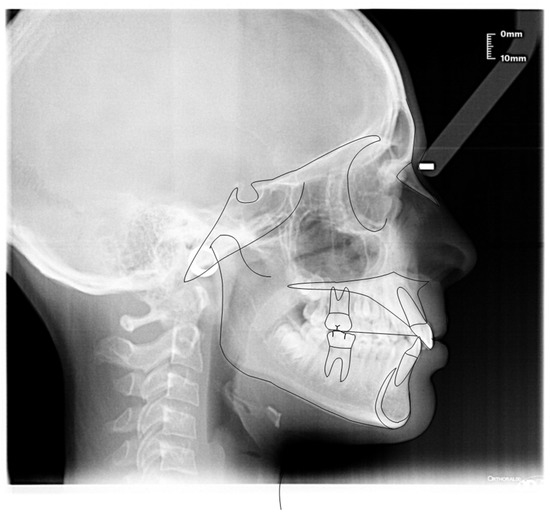

3.1. Clinical Case #1